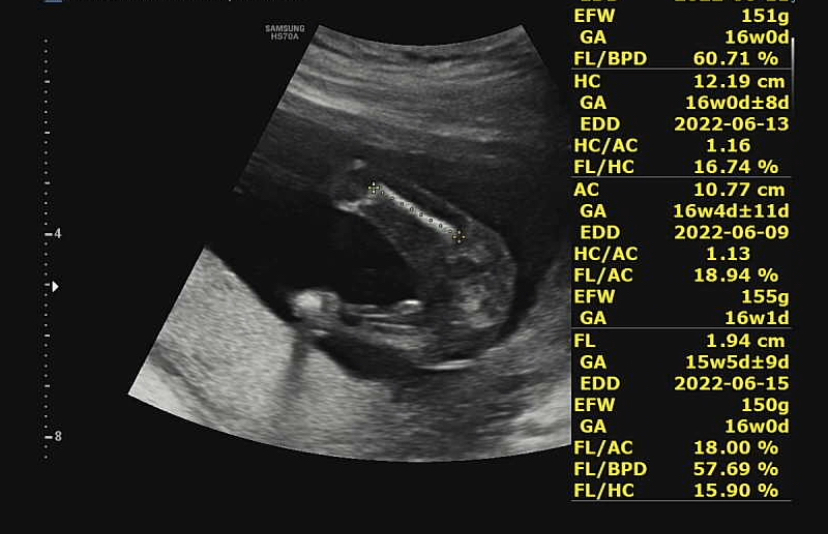

16주가 돼서 아기가 많이 자라서 한 초음파 화면에 다 잡히지 않는다. 그래서 머리-몸통-다리처럼 한 부위씩 돌면서 초음파를 봤다.

제일 먼저 본 머리! 뇌가 잘 정착해서 성장하고 있다고 했다. 뇌 중간 부분의 길이도 쟀지만 어떤 부위였는지는 잘 기억나지 않는다^^;처음 듣는 부위였던 것 같다.